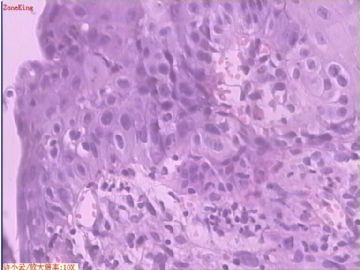

贲门息肉?

姓    名: ××× 性别:  女 年龄:  53

简要病史:  胃镜见,食道下段齿状线上可见一圆形隆起,有蒂,表面光滑,大小0.5X0.5X0.3cm.

各位老师,胃粘膜处出现的鳞状上皮有问题么?

• 贲门息肉?图3

图3

正好是齿状线腺鳞交界处粘膜

鳞状上皮没大问题,可能受炎症影响,稍有增生.

没有发现恶性证据,小心点儿可以拖个尾巴,譬如伴轻度异型增生。

本帖最后由 于 2009-11-21 09:51:00 编辑   谢谢各位老师指点,最终诊断为:贲门慢性炎症,伴局灶细胞轻度异型增生。